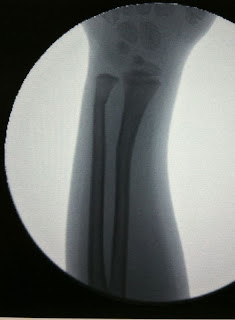

The orthopedic doctor had a cool xray machine in his office. He had to cut the plaster cast off so that he could take the xrays. Then we found out that two of her bones were bent, not just one. He put her in a fiberglass cast that glows in the dark. She was so brave through the whole thing. She did whimper a bit when he was putting her arm in a good position to heal correctly.